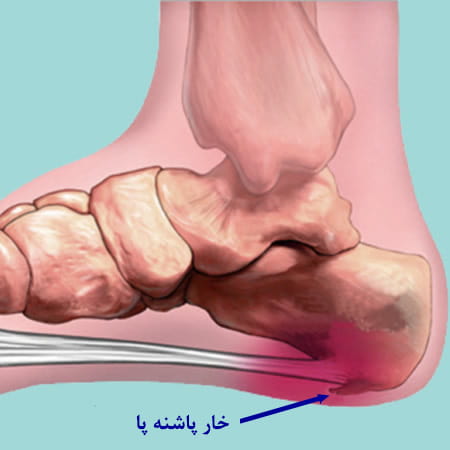

خار پاشنه

کلیپ آموزشی نحوه ایجاد خار پاشنه